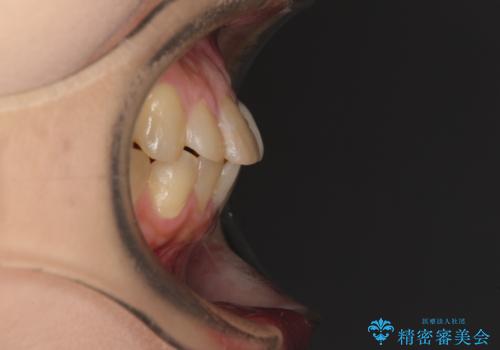

抜歯矯正により口元を引っ込めることも検討しましたが、特に口元の突出感は気になっていないとのことで、非抜歯にてワイヤー装置で矯正治療を行うこととしました。

舌の突出癖により治療期間中に開咬となり、治療が長引きましたが、口元も治療前よりも引っ込めることができ、すっきりとした仕上がりとなりました。